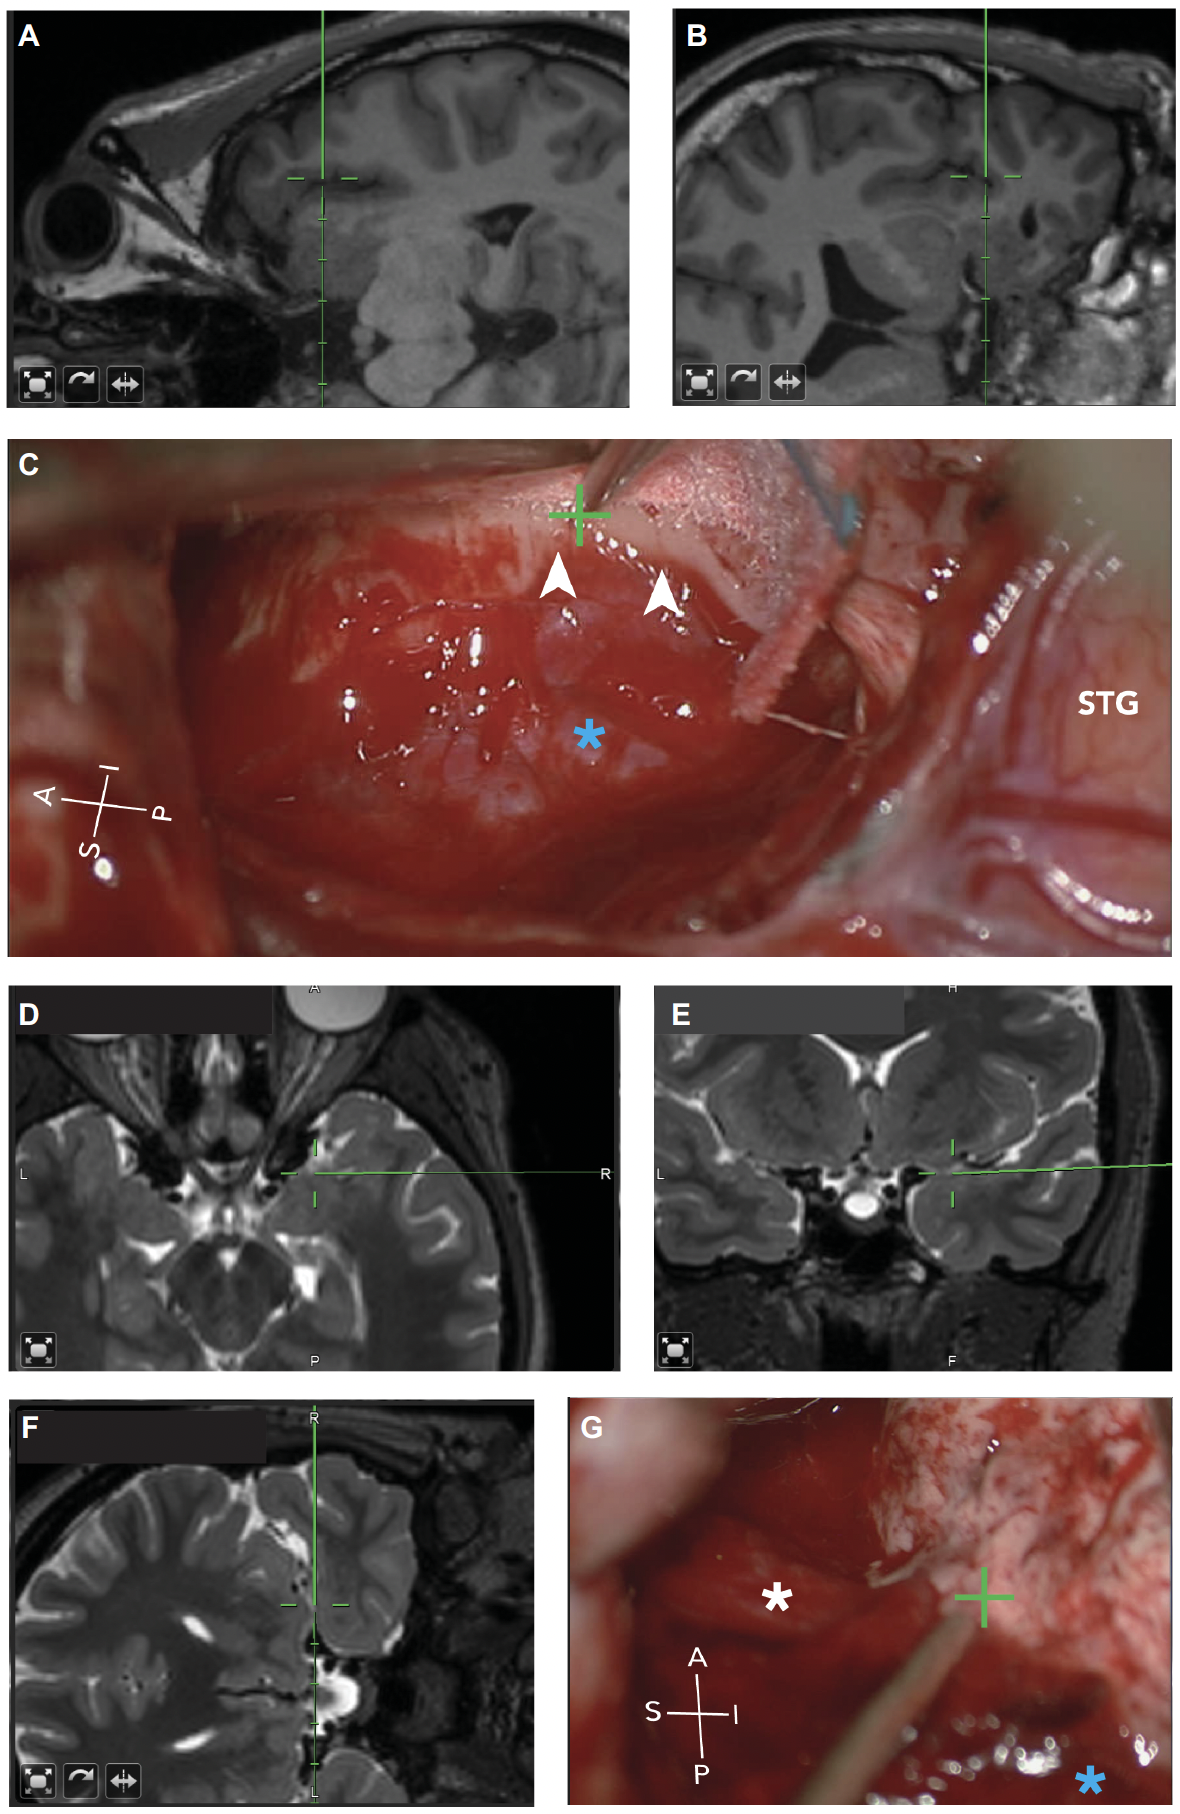

The Brain Modulation Lab has contributed to advancing both resective and neuromodulatory surgical approaches for drug-resistant epilepsy. In the domain of temporal lobe epilepsy surgery, we developed and reported a standardized extrapial hippocampal resection technique for anterior temporal lobectomy, demonstrating in a 62-patient case series that this approach yields seizure freedom rates of 79% (follow-up <3 years) and 52% (follow-up >3 years), with a low complication rate and consistent recovery of en bloc hippocampal specimens suitable for translational research (Hussein et al., Operative Neurosurgery, 2021). We also demonstrated that intracranial monitoring equalizes seizure outcomes in patients with nonconcordant presurgical data, with SEEG being the only approach used for bilateral or poorly lateralized temporal lobe epilepsy and resulting in 77.8% seizure freedom, notably with 85% of SEEG patients having their primary surgical hypothesis modified by the intracranial data (Sokolov et al., Epilepsia Open, 2022). Mike Modo’s lab at the University of Pittsburgh leveraged en bloc hippocampal specimens generated by the extrapial technique, to perform ex vivo mesoscale diffusion MRI that bridges the gap between macroscopic imaging and microscopic histopathology. This work began with the first demonstration that aberrant mossy fiber connections (a putative substrate for reverberant excitatory circuits in mesial temporal sclerosis) could be visualized using mesoscale diffusion MRI with histological validation (Modo et al., Human Brain Mapping, 2016), followed by systematic optimization of acquisition parameters for mesoscale hippocampal imaging (Ly et al., Human Brain Mapping, 2020) and the finding that intra-hippocampal diffusion metrics correlate with preoperative seizure frequency, providing a potential microstructural biomarker linking tissue pathology to clinical severity (Ke et al., Human Brain Mapping, 2020).